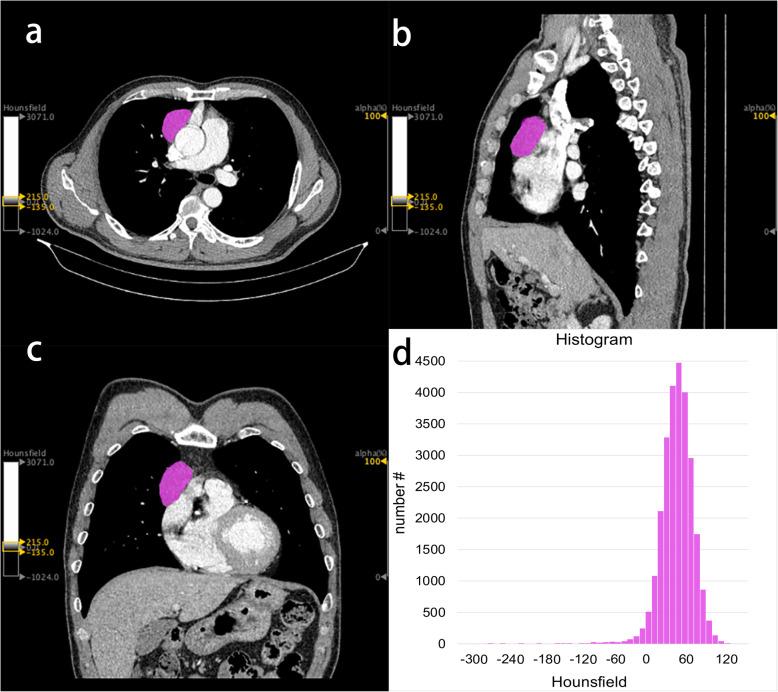

Thymic epithelial tumors (TETs) are the most common primary tumors in the anterior mediastinum, which have considerable histologic heterogeneity. This study aimed to develop and validate a nomogram based on computed tomography (CT) and texture analysis (TA) for preoperatively predicting the pathological classifications for TET patients.

METHODS

Totally TET 172 patients confirmed by postoperative pathology between January 2011 to April 2019 were retrospectively analyzed and randomly divided into training (n = 120) and validation (n = 52) cohorts. Preoperative clinical factors, CT signs and texture features of each patient were analyzed, and prediction models were developed using the least absolute shrinkage and selection operator (LASSO) regression. The performance of the models was evaluated and compared by the area under receiver-operator characteristic (ROC) curve (AUC) and the DeLong test. The clinical application value of the models was determined via the decision curve analysis (DCA). Then, a nomogram was developed based on the model with the best predictive efficiency and clinical utility and validated using the calibration plots.

RESULTS

Totally 87 patients with low-risk TET (LTET) (types A, AB, B1) and 85 patients with high-risk TET (HTET) (types B2, B3, C) were enrolled in this study. We separately constructed 4 prediction models for differentiating LTET from HTET using clinical, CT, texture features, and their combination. These 4 prediction models achieved AUCs of 0.66, 0.79, 0.82, 0.88 in the training cohort and 0.64, 0.82, 0.86, 0.94 in the validation cohort, respectively. The DeLong test and DCA showed that the Combined model, consisting of 2 CT signs and 2 texture parameters, held the highest predictive efficiency and clinical utility (p < 0.05). A prediction nomogram was subsequently developed using the 4 independently risk factors from the Combined model. The calibration curves indicated a good consistency between the actual observations and nomogram predictions for differentiating TET classifications.

CONCLUSION

A prediction nomogram incorporating both the CT and texture parameters was constructed and validated in our study, which can be conveniently used for the preoperative individualized prediction of the simplified histologic subtypes in TET patients.